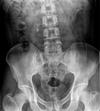

A 47-year-old male with right flank pain. (a) A magnified view from a control film of an intravenous urogram (IVU) demonstrates a 2 cm opacity in the right upper quadrant (arrow). This image clearly shows that the opacity is made up of multiple tiny calculi rather than a single large calculus, which should raise the suspicion that they lie within a calyceal diverticulum. (b) An oblique radiograph from a retrograde pyelogram study elegantly depicts the short, narrow infundibulum of a calyceal diverticulum arising from a mid-pole calyx (arrow).